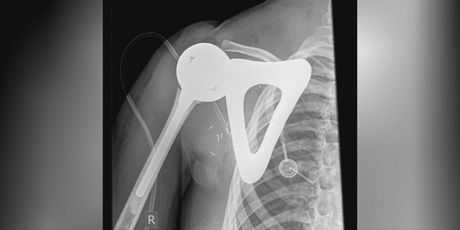

Odlične vijesti za hrvatsko zdravstvo! Korak dalje u primjeni tehnologije u medicini otišla je klinika za ortopediju Lovran. Desetodišnjak je dobio novu koštanu strukturu ramena isprintanu 3D printerom.

Novo rame, lopatica i dio nadlaktične kosti su izrađeni pomoću 3D printera i ugrađeni 10-godišnjem pacijentu u lovranskoj bolnici.

Tu se radilo o jednom vrlo agresivnom tumoru koji je praktički konzumirao cijelo rame djeteta. U takvoj situaciji kod konvencionalnih mjera, odnosno načina liječenja, bi došlo u obzir amputacija ili jedan oblik takozvano 'viseće rame', gdje se moraju apsolutno odstraniti tumor, a samim time i sve ostale koštane strukture, pojasnio je Branko Šestan, ravnatelj klinike za ortopediju Lovran za Dnevnik Nove TV.

Taj je složen proces prvi kao takav u Hrvatskoj. Operacija je trajala sedam sati. Ako uspoređujete s jednim običnim, nazovimo umjetnim ramenom koje je standardno, i redovno gdje je reda veličine između 10.000-15.000 kuna ovo je negdje reda veličine 250.000 kuna, istaknuo je Šestan.